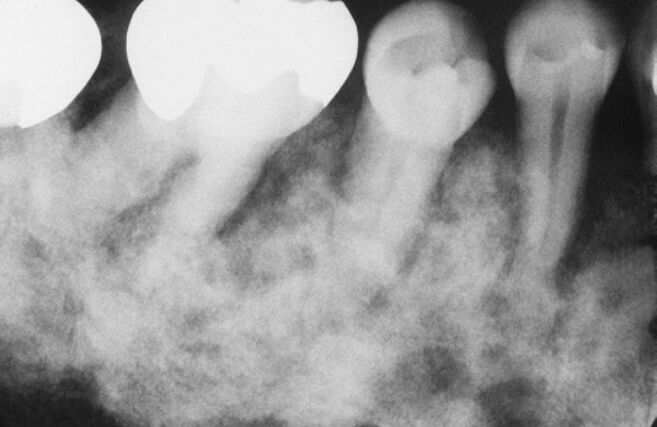

73.附圖X光片影像,在何種疾病中最易觀察到? (A)戈林症狀群(Gorlin syndrome)(B)柏哲德氏病(Paget disease)(C)骨化纖維瘤(ossifying fibroma)(D)顱顏面骨發育不全(craniofacial dysostosis)

74.附圖X光片影像,最可能是下列何種疾病? (A)骨化纖維瘤(ossifying fibroma) (B)纖維發育不良(fibrous dysplasia) (C)牙骨質-骨質發育不良(cemento-osseous dysplasia) (D)成纖維性纖維瘤(desmoplastic fibroma)